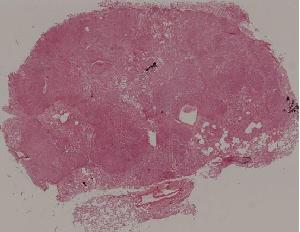

89.淋巴结结核